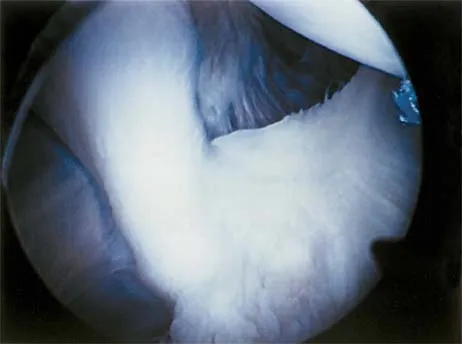

A baseball pitcher has intractable posterior and superior shoulder pain. The arthroscopic view seen in Figure 25 shows no Bankart or Hill-Sachs lesion and a negative drive-through sign. There are no signs of ligamentous laxity, but active compression and anterior slide tests are positive. Treatment should consist of

Explanation